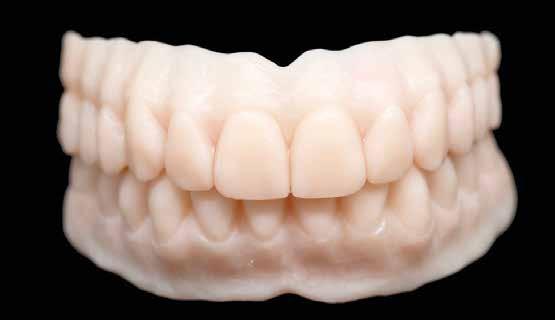

A páciens évekkel ezelőtt két mukozális megtámasztású kivehető fogsort kapott. Az atrófia következtében ezek már nem rögzülnek megfelelően. Implantátumokat terveztünk pillérként. A csekély csontkínálat és az egyszerűbb kezelhetőség okán négy rövid implantátumot (Bicon, Bosten) helyeztünk be. Végleges pótlásként teleszkóp elhorgonyzású redukált alaplemezű kivehető fedőfogsort terveztünk. A fogorvos intraorális szkennerrel beolvasta az alsó és felső állcsontot. Ehhez becsavarta az implantátumokba a megfelelő scanbody-kat (digitális lenyomatvételi fej - a ford.) (rövid UA-Scan-post, Bicon, 2. kép). Mivel a régi fogsorral komfortosnak érezte a harapást a páciens, ez segített a harapásregisztrációban. A helyzet rögzítésére vesztibulárisan beszkennelte az orvos a behelyezett fogsorokat. Végül a két fogsort szájon kívül is, egészében beolvasták a Medit IO-szkennerrel (Szöul). Utoljára portréfotó

készült. Minden így nyert adatot interneten a laboratóriumba küldtek. A végleges elkészítéséig a páciens hordja tovább régi fogsorait. Nem volt szükség további találkozásokra sem ideiglenes fogsor készítéséhez, sem a harapásregisztrációhoz és laborban készített sablonok próbájához sem.

Fogtechnikai labor:

A laboratóriumban az összes adatot összefűztük egy „digitális pácienssé” a darmstadti exocad DentaCad rendszerében. Az állcsontokat a vesztibuláris fogsorbeolvasással illesztettük térben egymáshoz (3. kép). Az implantátumok helyzetét a fejek mutatták meg. A külön beszkennelt fogsorokat pedig mock-up-ként tudtuk használni a tervezés során (4. kép). A páciens portréját rávetítettük a frontra, így segítve az esztétikai ellenőrzést (5. kép)